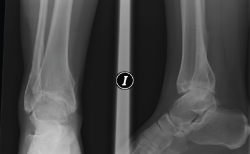

Figura 6. Artrosis postraumática de tobillo tras fractura bimaleolar hace 15 años.

Figura 8. Caso de la Figura 6 a los 3 años de la distracción articulada. Obsérvese el mantenimiento del espacio articular a nivel de la articulación del tobillo.